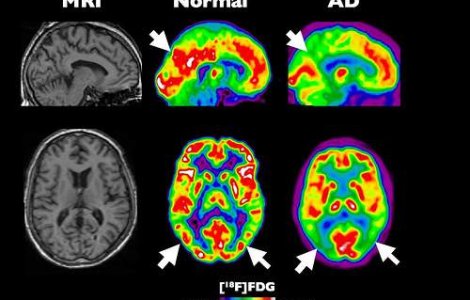

Un dispozitiv cu ultrasunete ar putea sta la baza unui tratament revolutionar impotriva maladiei Alzheimer.